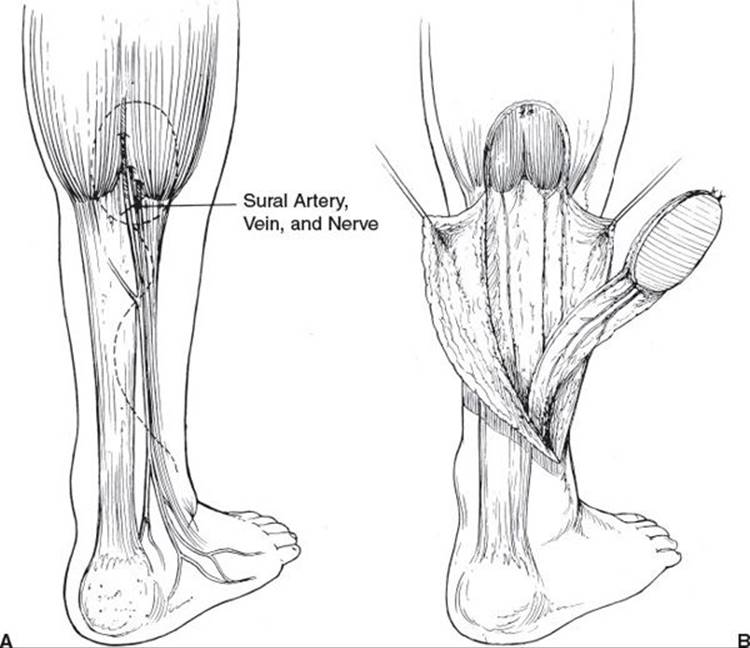

The retrograde sural nerve flap (Figure 95.5) is a versatile neurofasciocutaneous flap that is useful for ankle and heel defects. The sural artery travels with the sural nerve and receives retrograde flow from a peroneal perforator 5 cm above the lateral malleolus. The artery first courses above the fascia and then penetrates deep to the fascia at midcalf while the accompanying lesser saphenous vein remains suprafascial. The venous congestion often seen with this flap can be minimized if the pedicle is harvested with 3 cm of tissue on either side of the pedicle and with the overlying skin intact. Problems with venous drainage can be further helped if the flap is delayed, 4 to 10 days earlier, by ligating the proximal lesser saphenous vein and sural artery. The inset of the flap is critical to avoid kinking of the pedicle. Ingenious splinting is necessary to avoid pressure on the pedicle while the flap heals (the Ilizarov external frame can be useful in this regard). The major donor deficit of the flap is the loss of sensibility along the lateral aspect of the foot, while the skin-grafted depression in the posterior calf may pose a problem if the patient subsequently has a below-the-knee amputation. To minimize donor defect, this flap can be dissected out as a perforator flap.

FIGURE 95.5. Retrograde sural artery flap. This flap depends on a peroneal perforator 5 cm proximal to the lateral malleolus. It also includes the lesser saphenous vein. Use of the flap sacrifices the sural nerve, leaving the lateral foot insensate. It is useful in covering lower leg, ankle, and hindfoot defects. A. Flap design. B. Flap dissection and arc of rotation. (From Attinger C. Soft tissue coverage for lower extremity trauma. Orthop Clin North Am. 1995;26:3, with permission.)